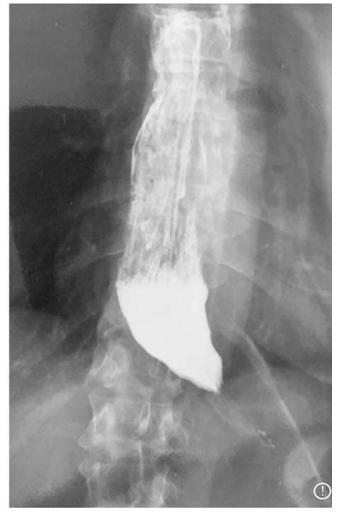

Considerando a figura acima, assinale a alternativa que apresenta a opção terapêutica que está fora do padrão de tratamento para essa situação, em paciente com exame endoscópico com esofagite e nunca tratado previamente.

Quanto à realização de uma fundoplicatura para a correção da doença do refluxo, assinale a alternativa correta.